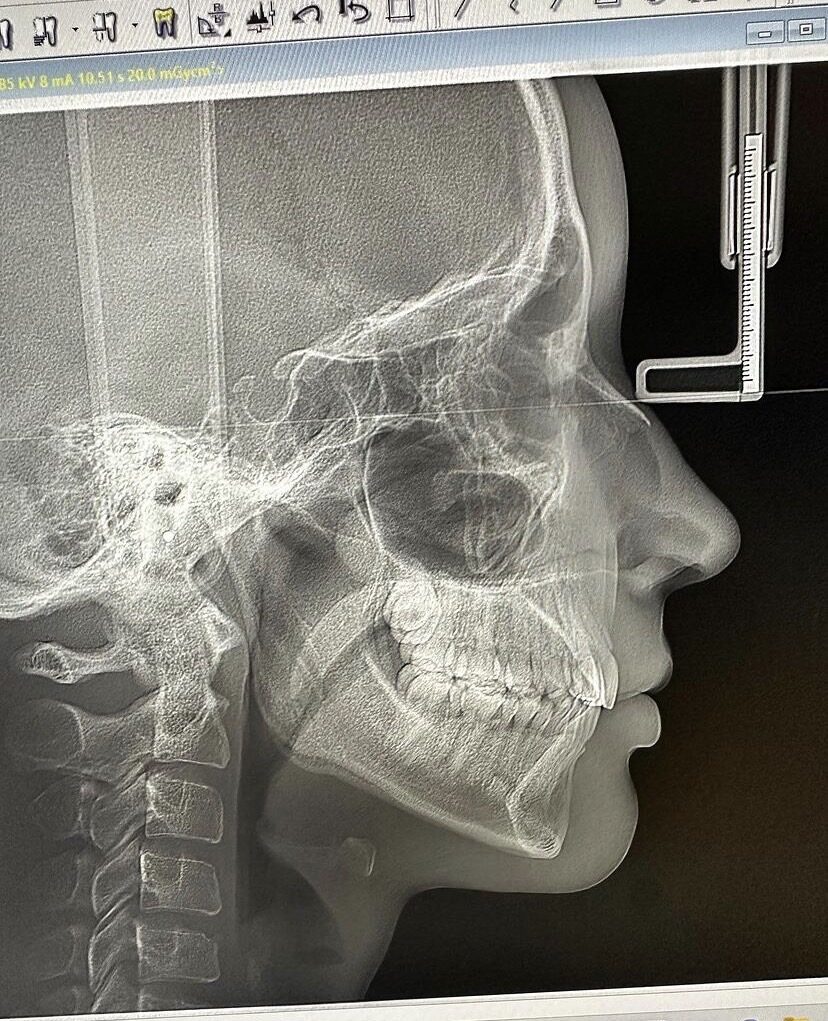

ลูกรักพระเจ้า! ชาวเน็ตอึ้ง ฟิล์มเอกซเรย์ "โยชิ รินรดา ธุระพันธ์" สวยยันกระดูก แห่อวยความปัง ออร่าจับ โครงหน้าพระเจ้าปั้น

ล่าสุด 'โยชิ' ก็สร้างกระแสฮือฮาในโลกโซเชียลอีกครั้ง เมื่อเจ้าตัวออกมาโพสต์ภาพ'ฟิล์มเอกซเรย์' ที่หลายคนเห็นแล้วถึงกับอึ้ง โดยเธอได้มีโอกาสเข้าไปปรึกษาหมอฟัน พร้อมให้เหตุผลในแคปชั่นว่า "คนขี้เกียจใส่รีเทนเนอร์แบบเราก็ฟันล้มสิคะ เริ่มจัดใหม่ให้จึ้งกว่าเดิม"

โดยภาพ 'ฟิล์มเอกซเรย์' ดังกล่าว เผยให้เห็นสัดส่วนกระดูก และโครงหน้าที่ปังมากเวอร์ จนชาวเน็ตถึงกับคอมเมนต์แซวว่า 'สมกับเป็นลูกรักพระเจ้า โครงหน้าพระเจ้าปั้นมาก สวยยันกระดูก'

ส่งผลให้รูป 'ฟิล์มเอกซเรย์' ดังกล่าวกลายเป็นไวรัลโด่งดังในชั่วข้ามคืน ชาวเน็ตต่างแชร์ภาพไปทั่วโลกออนไลน์ พร้อมชื่นชมความสวยปังของ 'โยชิ' กันอย่างล้นหลาม